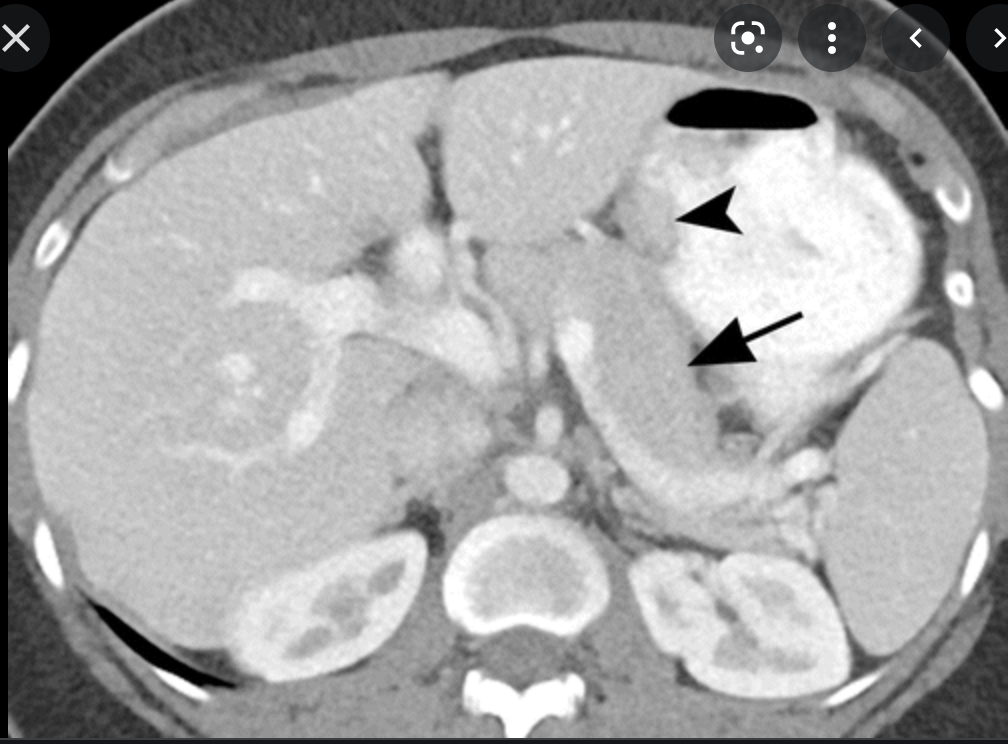

Single phase CT scan (multiphase scans not performed due to age of patient) demonstrates a diffusely enlarged pancreas with a “halo” like rim of hypoattenuating tissue which is smoothly marginated. Minimal peripancreatic fat stranding.

Associated splenic vein thrombosis, splenomegaly and cavernous transformation of the portal vein.